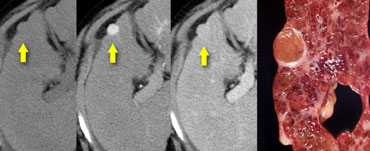

NECT, arterial and portal venous phase in a patient with Hepatitis C with two lesions in the liver (arrows). NECT, arterial and portal venous phase in a patient with Hepatitis C with two lesions in the liver (arrows).

In the arterial phase we see two hypervascular lesions.

Now do not just concentrate on the images, where you see the lesions best.

You have to look at all the other images, because they give you the clue to the diagnosis.

The upper images show a lesion that is isodens to the liver on the NECT.

In the arterial phase there is enhancement, but not as dense as the bloodpool.

In the portal venous phase the lesion is again isodense to the surrounding liver parenchyma and you can't see it.

If you only had the portal venous phase you surely would miss this lesion.

The lower images show a lesion that is visible on all images.

You see it on the NECT and you could say it is hypodens compared to the liver.

Does this help you?

No, not in the least.

However if you look at the bloodpool, you will notice that on all phases it is as dense as the bloodpool.

So we have a HCC in the right lobe on the upper images and a hemangioma in the left lobe on the lower images.

The key is to look at all the phases.